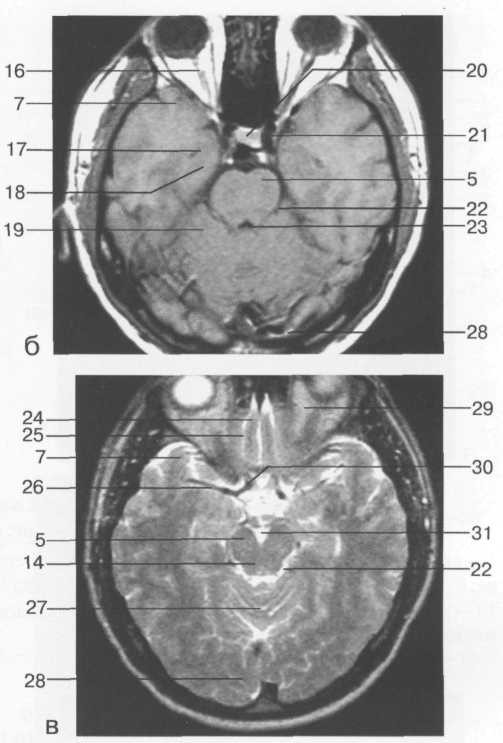

При изучении структур мозги МРТ имеет некоторые преимущества перед КТВо-первых, на MP-томограммах более четко различаются структурные элементы головного мозга, отчетливее дифференцируются белое и серое вещество, все стволовые структуры. На качестве магнитно-резонансных то­мограмм не отражается экранирующее действие костей черепа, ухудшаю­щее качество изображения при КТ. Во-вторых, МРТ можно производить в разных проекциях и получать не только аксиальные, как при КТ, но и фронтальные, сагиттальные и косые слои. В-третьих, это исследование не связано с лучевой нагрузкой. Особым достоинством МРТ является возмож­ность отображения сосудов, в частности сосудов шеи и основания головно­го мозга, а при контрастировании гадолинием -- и мелких сосудистых вет­вей (см. рис. 35 и 36).

Рис. 36. Изображения аксиальных срезов КТ и МРТ области головы над уровнем  четвертого желудочка:

а -- аксиальный срез КТ; б -- аксиальный срез МРТ

(Т1-ВИ); в -- аксиальный срез МРТ (Т2-ВИ).

1 -- лобная доля; 2 -- лобный рог бокового желудочка; 3 -- латеральная щель мозга; 4 -- третий желудочек; 5 -- ножка мозга; 6 -- цистерна четверохолмия; 7 -- височная доля; 8 -- верхний сагиттальный синус; 9 -- серп мозга; 10 -- головка хвостатого ядра; 11 -- кора островка; 12 -- скорлупа; 13 -- внутренняя вена мозга; 14 -- четверохолмие; 15 -- полушарие мозжечка; 16 -- зрительный нерв; 17 -- височный рог бокового желу­дочка; 18 -- гиппокамп; 19 -- передняя долька мозжечка; 20 -- хиазма; 21 -- внутренняя сонная артерия; 22 -- охватывающая цистерна; 23 -- четвертый желудочек; 24 -- прямая извилина; 25 -- ольфакторная бо­розда; 26 -- средняя мозговая артерия; 27 -- червь; 28 -- затылочная доля; 29 -- клетчатка орбиты; 30 -- пе­редняя мозговая артерия; 31 -- межножковая цистерна.

Представленные изображения  в полной мере дают возможность оценить структуры головного мозга.